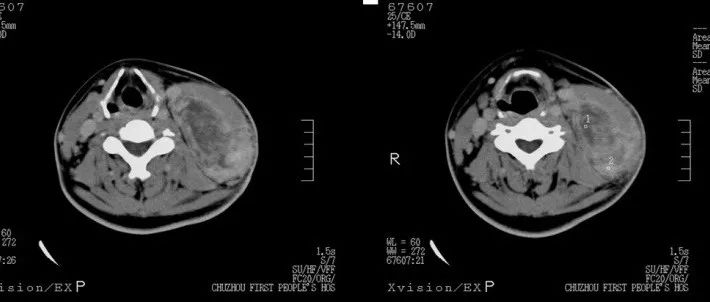

中年男性,左侧颈部包块两月余,请诊断!

医学影像  yxyx-app  医学影像APP,打造伴随医生快速成长的影像学习社区。与影像园(Xctmr.com)一起提供最全面的影像案例库、基础(解剖、病理、影像诊断)知识、影像技术及考题等,为医生提供最佳的医学影像参考。【所属科室】普外科【基本资料】患者,男,40岁【主诉】左侧颈部包块两月余【影像图片】【讨论问题】如何诊断?【医学影像APP用户讨论】评论:...

医学影像APP 2022-08-29